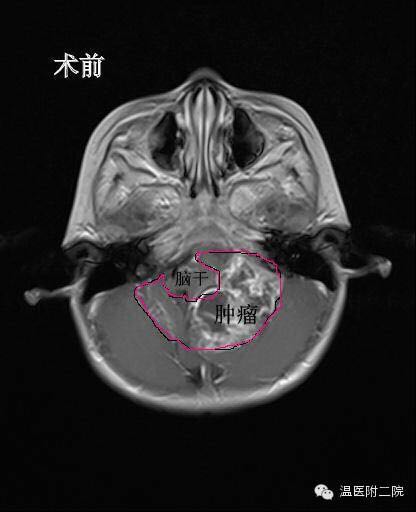

医生给俊俊做了脑部CT和核磁共振,检查的结果让该院儿童神经外科主任林坚大吃一惊:“后脑长了鹅蛋大小的一个肿瘤,直径有7cm*5cm*6.5cm。”这颗巨大的肿瘤紧紧包住了四分之三的脑干和好几条神经血管,手术风险极大。

第二步要做的就是清除掉俊俊脑内的巨大肿瘤——把肿瘤和脆弱的脑干以及细小的神经血管精确地剥离,并且还要确保不能伤到脑干和血管。经过6个多小时的手术,俊俊脑内的“鹅蛋”被清理。在对肿瘤进行病理切片分析之后,确认俊俊的脑瘤是室管膜瘤三级,属于恶性肿瘤,需要进一步放化疗。